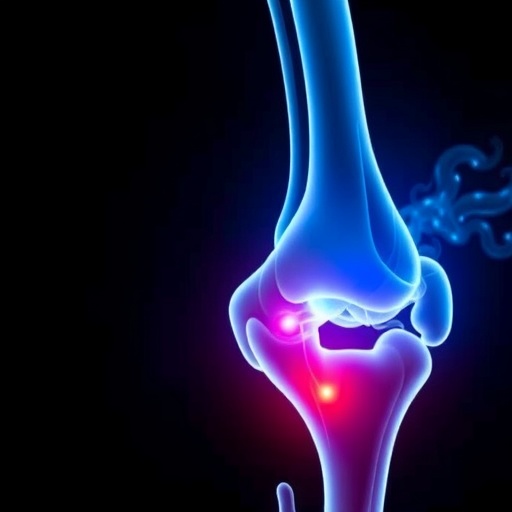

The optimization of bone cement stiffness is a complex interplay between material properties and the biomechanical demands placed on the spine. The authors begin by elucidating the vital role that properly formulated bone cements play in restoring not just the structural integrity of the vertebrae but also in mitigating pain and enhancing mobility in patients. In metastatic vertebral augmentation, where the foundational structure of the spine is compromised, the stiffness of the cement becomes a critical factor. Too rigid a cement might lead to stress shielding, where the surrounding bone bears an undue share of the load, while too pliable a formulation could give rise to mechanical failure under relatively low loads.

The study introduces a variety of experimental and computational methods designed to analyze the optimal stiffness characteristics of bone cement. By employing finite element analysis, the researchers simulate different loading conditions that the augmented vertebra would undergo in a typical scenario. This computational approach allows for an exploration of how varying stiffness levels influence the stress distribution not only in the cement itself but also across adjacent vertebral bodies. Such modeling is crucial for predicting how changes in one part of the system can affect the entire biomechanical landscape of the spine.

One of the fascinating outcomes of this study revolves around the identification of an ideal stiffness range for bone cement. The researchers present data suggesting that a moderate stiffness provides the most favorable conditions for load sharing. This nuance is critical; it underscores the necessity of achieving a balance that prioritizes both the restoration of bone integrity and the preservation of the natural stress distribution within the vertebral column. Their findings indicate a clear relationship between cement stiffness, vertebral body strength restoration, and the reduction of adjacent segment stress, presenting a breakthrough in the pursuit of restorative therapies for spinal health.